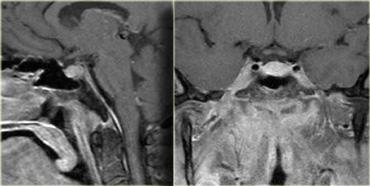

U thần kinh bao (Schwannoma) vùng góc cầu tiểu não với các đặc điểm điển hình của u ngoài trục (Chuỗi xung T2W)

Chuỗi xung T2W cho thấy một u thần kinh bao (schwannoma) nằm ở góc cầu tiểu não (CPA).

Trường hợp này minh họa rõ nét các dấu hiệu điển hình của u ngoài trục.

Có khe dịch não tủy (mũi tên vàng).

Các mạch máu dưới nhện chạy trên bề mặt não bị tổn thương đẩy lệch (mũi tên xanh lam).

Có chất xám nằm giữa tổn thương và chất trắng (mũi tên đỏ cong).

Khoang dưới nhện bị giãn rộng do sự phát triển của tổn thương ngoài trục có xu hướng đẩy lùi não.

Tất cả các dấu hiệu này cho thấy đây là một u ngoài trục điển hình.

Tại vùng góc cầu tiểu não, 90% các u ngoài trục là u thần kinh bao (schwannoma).